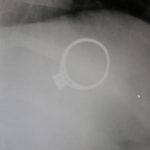

F.G. ve C.G. çiftinin 1,5 yaşındaki bebeği M.G. annesinin yüzüğünü aldı ve onunla oyun oynarken ağzına götürerek bir anda yüzüğü yuttu. Anne tarafından durumun fark edilmesinin hemen ardından Sivas Medicana Hastanesine götürülen bebeğin röntgeni çekildi ve tek taş yüzüğün mideye gittiği bilimsel olarka da tespit edildi. Günlerce gözetim altında kalan çocuk 6. gün içerisinde yüzüğü çıkartarak herkese derin bir oh çektirdi.